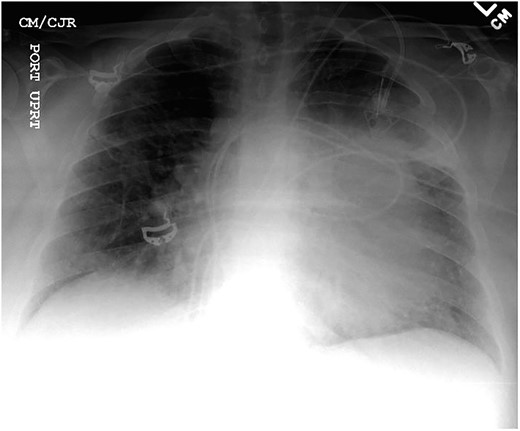

Chest X-ray found an enlarged cardiomediastinal silhouette with mild pulmonary edema (Fig. 1). A computed tomography angiography (CTA) of the chest to rule out pulmonary embolism (PE) was ordered. After the patient returned from imaging, she was found to have a heart rate of 178. Patient was awake, did not appear to be in any more distress and remained hemodynamically stable. Repeated ECG showed monomorphic ventricular tachycardia, with the patient remaining non-distressed. Patient was started on i.v. amiodarone, and urgent cardiology consult was obtained. A transthoracic echocardiogram depicted a large mass measuring 5 cm by 7 cm occupying the basal and mid portion of the anterior and lateral walls of the left ventricles with large pericardial effusion located at the lateral posterior wall of the heart, findings suggestive of impending tamponade (Fig. 2). CTA of the chest reported no acute PE with a large mass (10.5 × 7.5 × 9.5 cm3) occupying the anterior wall of the left ventricle and extending to the pulmonary outflow tract (Fig. 3).

Transthoracic echocardiogram depicting large effusion within pericardial membrane with left ventricular mass.